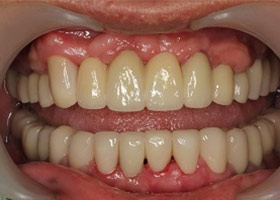

經由多顆人工植牙及全瓷假牙的全口重建,牙周病治療讓病人恢復咬合的功能與美觀,也易於每日的清潔保養。

治療後

proimages/Case/dentalimplant/10/02/after03.jpg